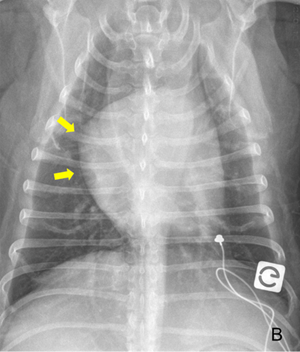

Atteinte pulmonaire interstitielle diffuse chez un WHWT Cardiomégalie droite

photo 4a photo 4b